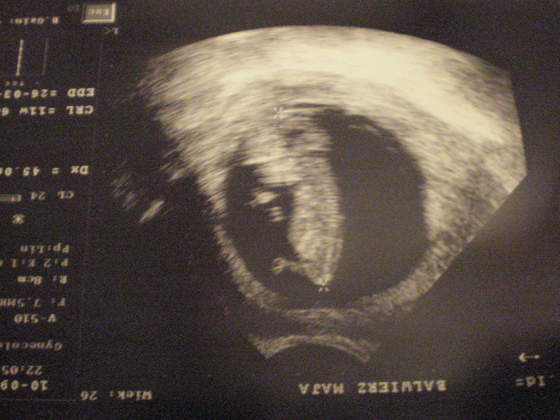

USG- Marcówki 2010

A oto moje Maleństwo ;)

• P9100204.jpg

P9100204.jpg

26,1 KB · Wyświetleń: 131